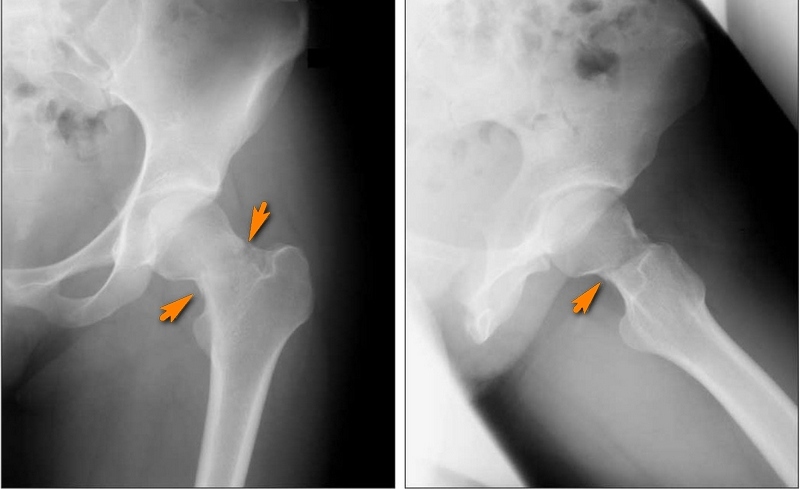

Диагностика

Диагностика основана на данных осмотра и анамнеза (указание на травмы, падения). Основной инструментальный метод диагностики перелома бедренной кости - рентгенографическое исследование. Использование компьютерной томографии в диагностике перелома бедренной кости позволяет точно определить сложность и степень костных повреждений.

Переломы шейки бедренной кости подразделяют на трансцервикальные, базальные и субкапитальные. В зависимости от механизма возникновения травмы они могут быть абдукционными и аддукционными (встречаются более часто).

Линия перелома может находиться за пределами сустава (внесуставной перелом) или проходить внутри его (внутрисуставной перелом).

Выделяют следующие виды внутрисуставного перелома бедра:

- капитальный - линия перелома расположена в области головки бедра;

- трансцервикальный (чрезшеечный) - линия перелома проходит в области шейки бедра;

- субкапитальный - линия перелома расположена под головкой;

- базисцервикальный - линия перелома проходит на границе перехода шейки в тело бедренной кости.